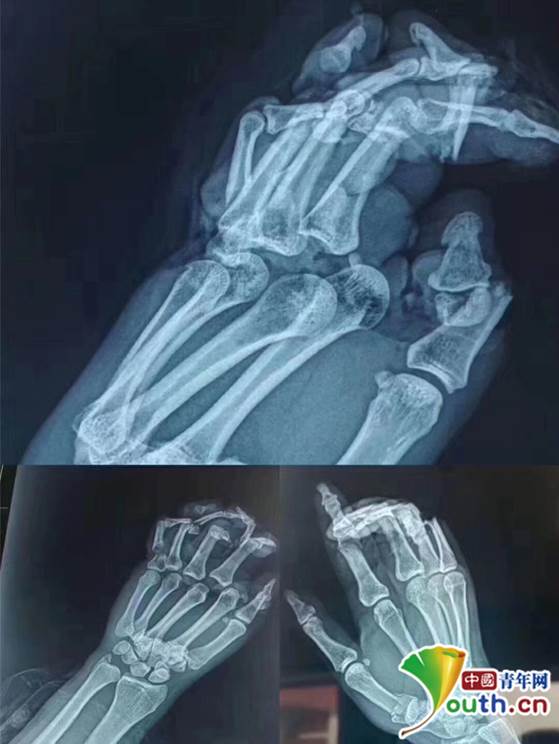

伤者手部X光片,腕关节脱位、手掌离断、骨折、手指多节段离断。受访者供图

15:00,2组医护人员同时对伤者左右手开展手术。“血管和神经都是撕裂性的损伤,2根小指已经没有正常结构”,手足外科医生李荣俊负责右手的手术,小指无再植条件,剩下的手指就尤为珍贵。7个多小时过去,李荣俊才下手术台休息了一小会,“喝点水活动下就上(手术台)去,时间不允许也没心情吃饭”。负责左手的周锦明也认为要和时间赛跑:“吃完就困了,头撞显微镜,你敢吃?不敢吃!”